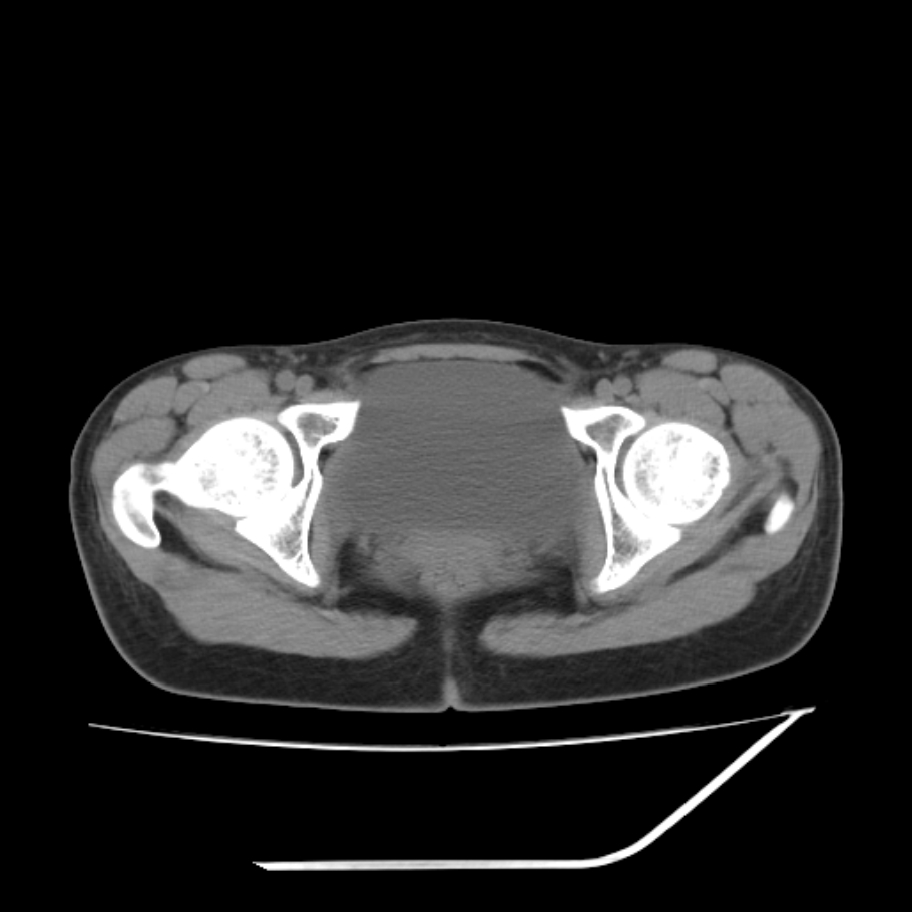

女,25岁。偶尔有右下腹不适感,余无明显异常。(结婚半年),囊壁较厚,是卵巢囊肿吗?

右侧卵巢区椭圆形囊性肿物,内壁光滑 无分隔。直肠子宫间隙内有少量积液征象。结合临床考虑卵巢巧克力囊肿,还要问问有没有痛经,本例ct怎么没有灌肠?要是灌肠或前一前口服造影剂,起码可以和肠管区别开

右侧囊性占位,1囊肿,2囊腺瘤。

b超示:囊实性占位,畸胎瘤?临床有痛经。

巧克力囊肿

考虑右侧卵巢囊性占位性病变(巧克力囊肿?),盆腔积液有不排除宫外孕可能,请结合临床和b超。